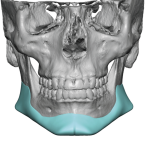

People considering custom jawline implants tend to ask a consistent set of questions. These generally fall into four categories: outcomes, safety, process, and recovery. What are custom jawline implants? Custom jawline implants are patient-specific implants designed from a 3D CT scan of your face. Unlike standard implants, they are digitally created to match your exact Read More…